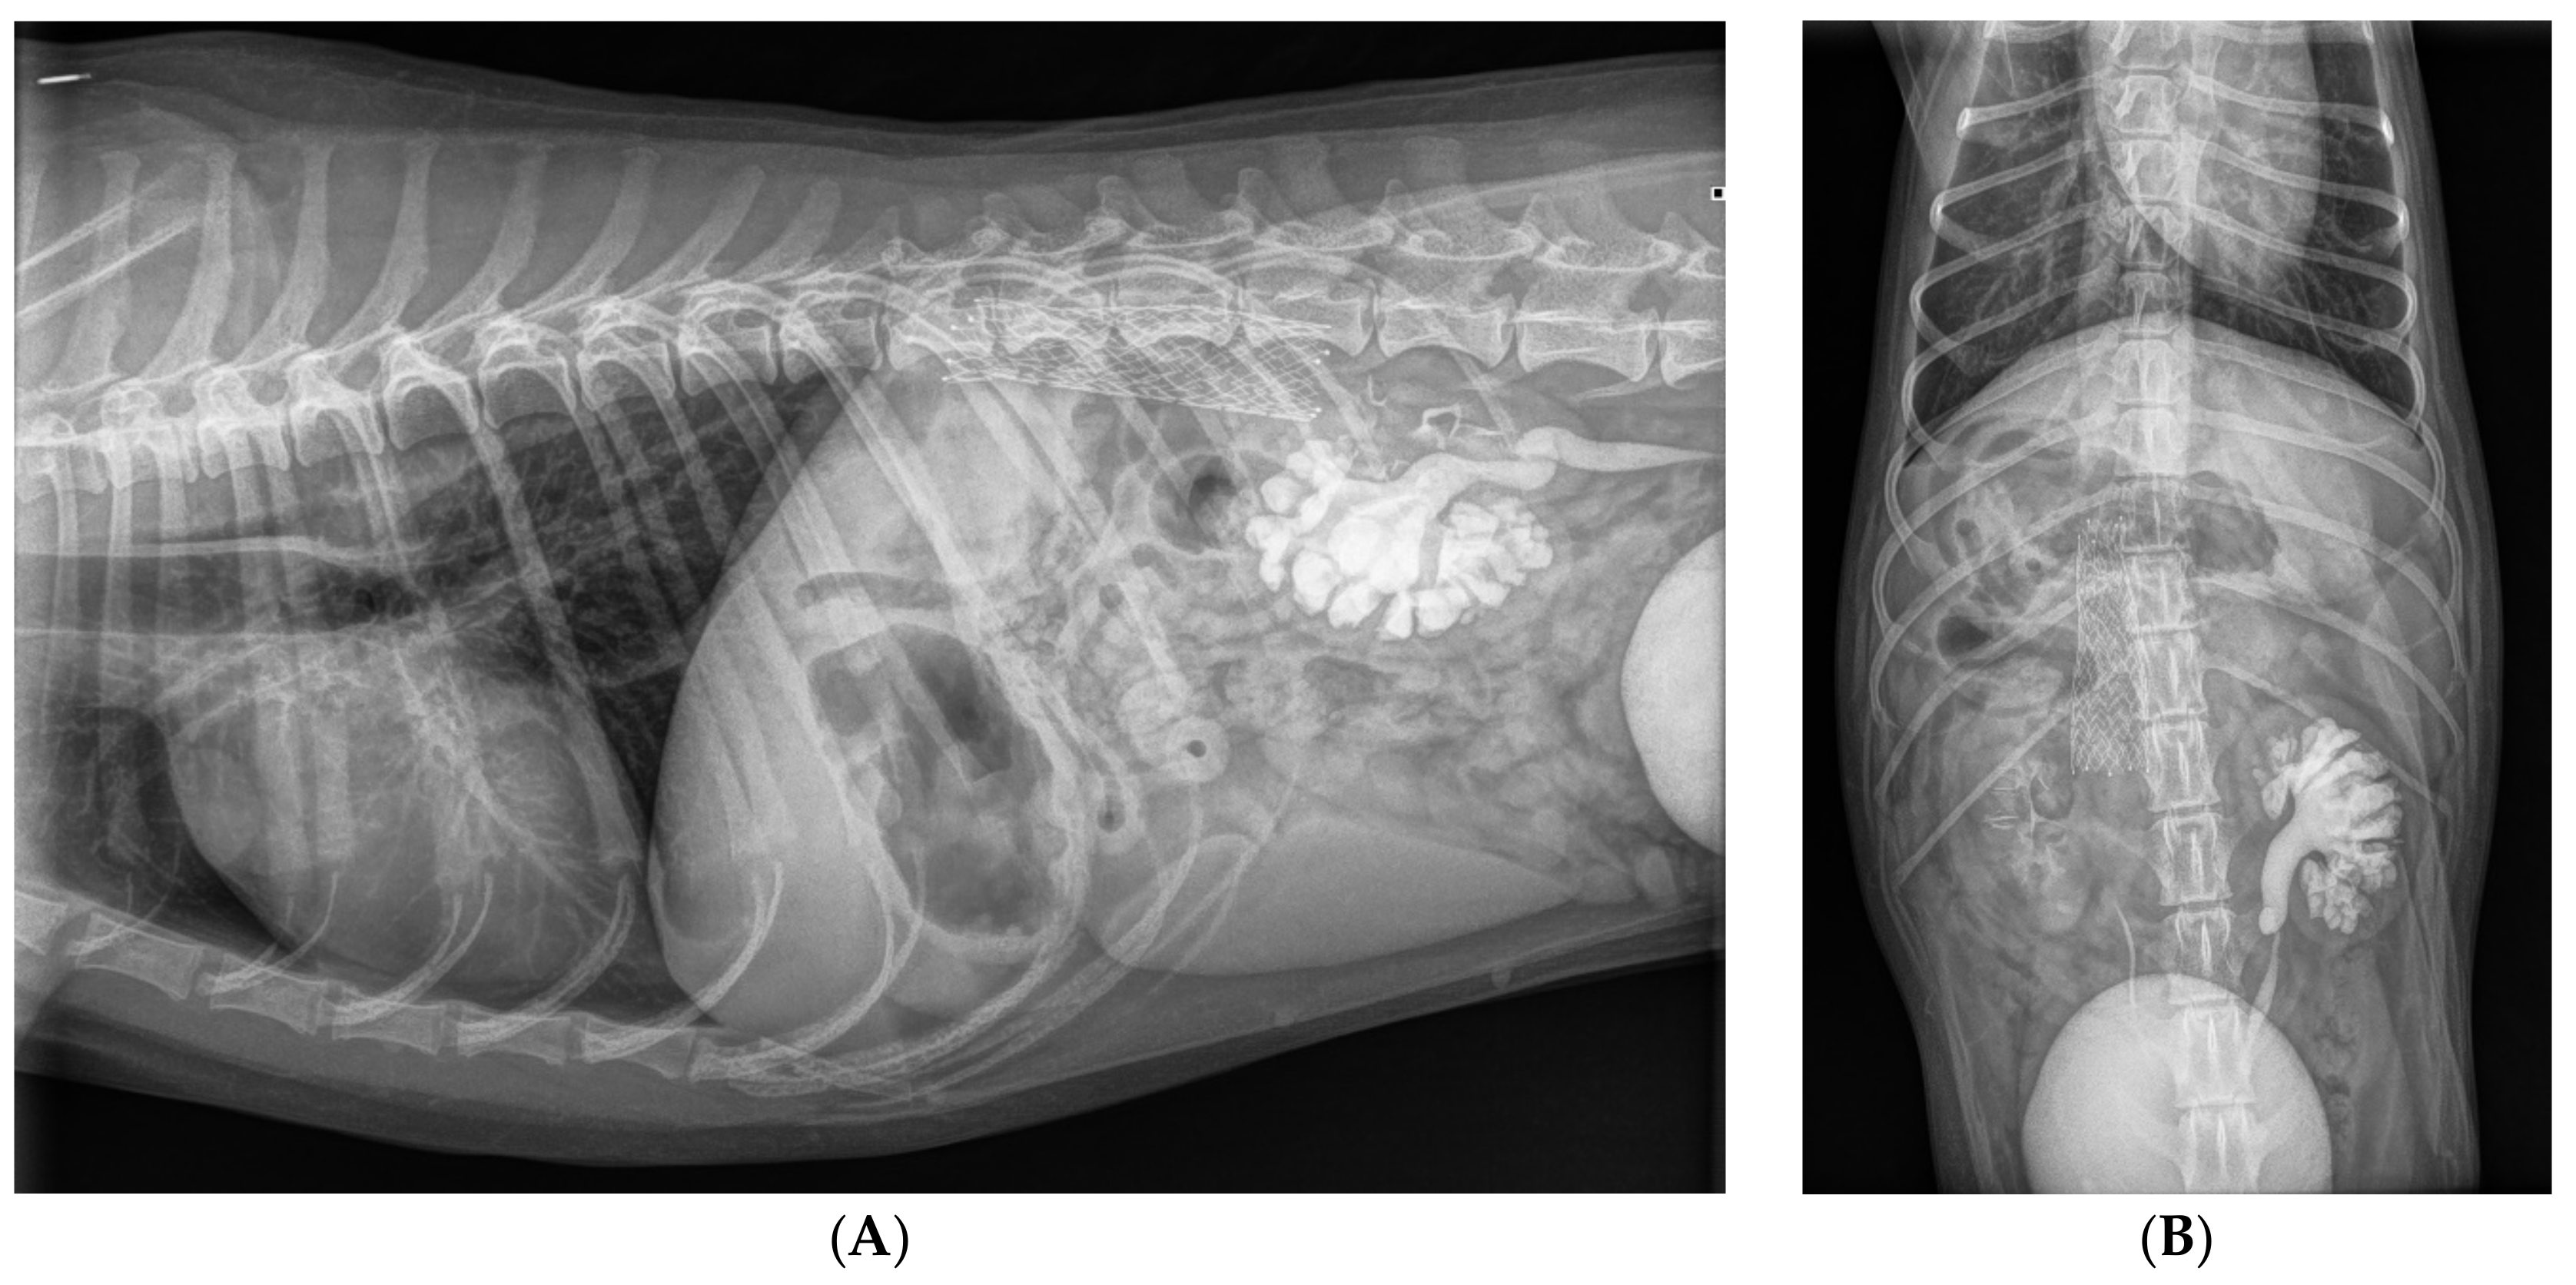

After removal of the stent delivery system, the angiographic catheter was reintroduced over the guidewire. After removal of the guidewire, an angiogram was performed with machinal injection of 7 mL of iodinated contrast agent (10 mL/sec, 1000 PSI). The angiogram showed a good positioning of the stent, where approximately 1 cm of the stent was positioned in the aneurysm (Figure 5B and 7B). There was a fast clearance of contrast with a good cranially directed flow in the CVC and azygos vein (Figure 5B). However, some contrast remained in the segment of the azygos vein where the stent was positioned for at least 20 s (Figure 7B). Inspiration facilitated blood flow in the azygos vein into cranial direction towards the heart. Invasive pressure measurement via the side-port of the introducer showed a mean pressure of 8 mmHg. After removal of the catheter and introducer, the skin incision was closed with a purse string suture. An intravenous dose of heparin (100 IU/kg) was administered. Postoperative radiographs were made to document the position and shape of the stent (Figure 8).

Figure 8. Radiographs in lateral (A) and in dorsoventral (B) projections made immediately after implantation of the stent in the right azygos vein. The stent is visible at the level of T12 to L1 vertebrae. As a result of renal excretion of the intravenously administered iodinated contrast material, the contrast is visible in the urinary bladder, both ureters and both kidneys. The left renal pelvis and the left ureter are moderately dilated as a result of an assumed compression of the retrocaval part of the left ureter.